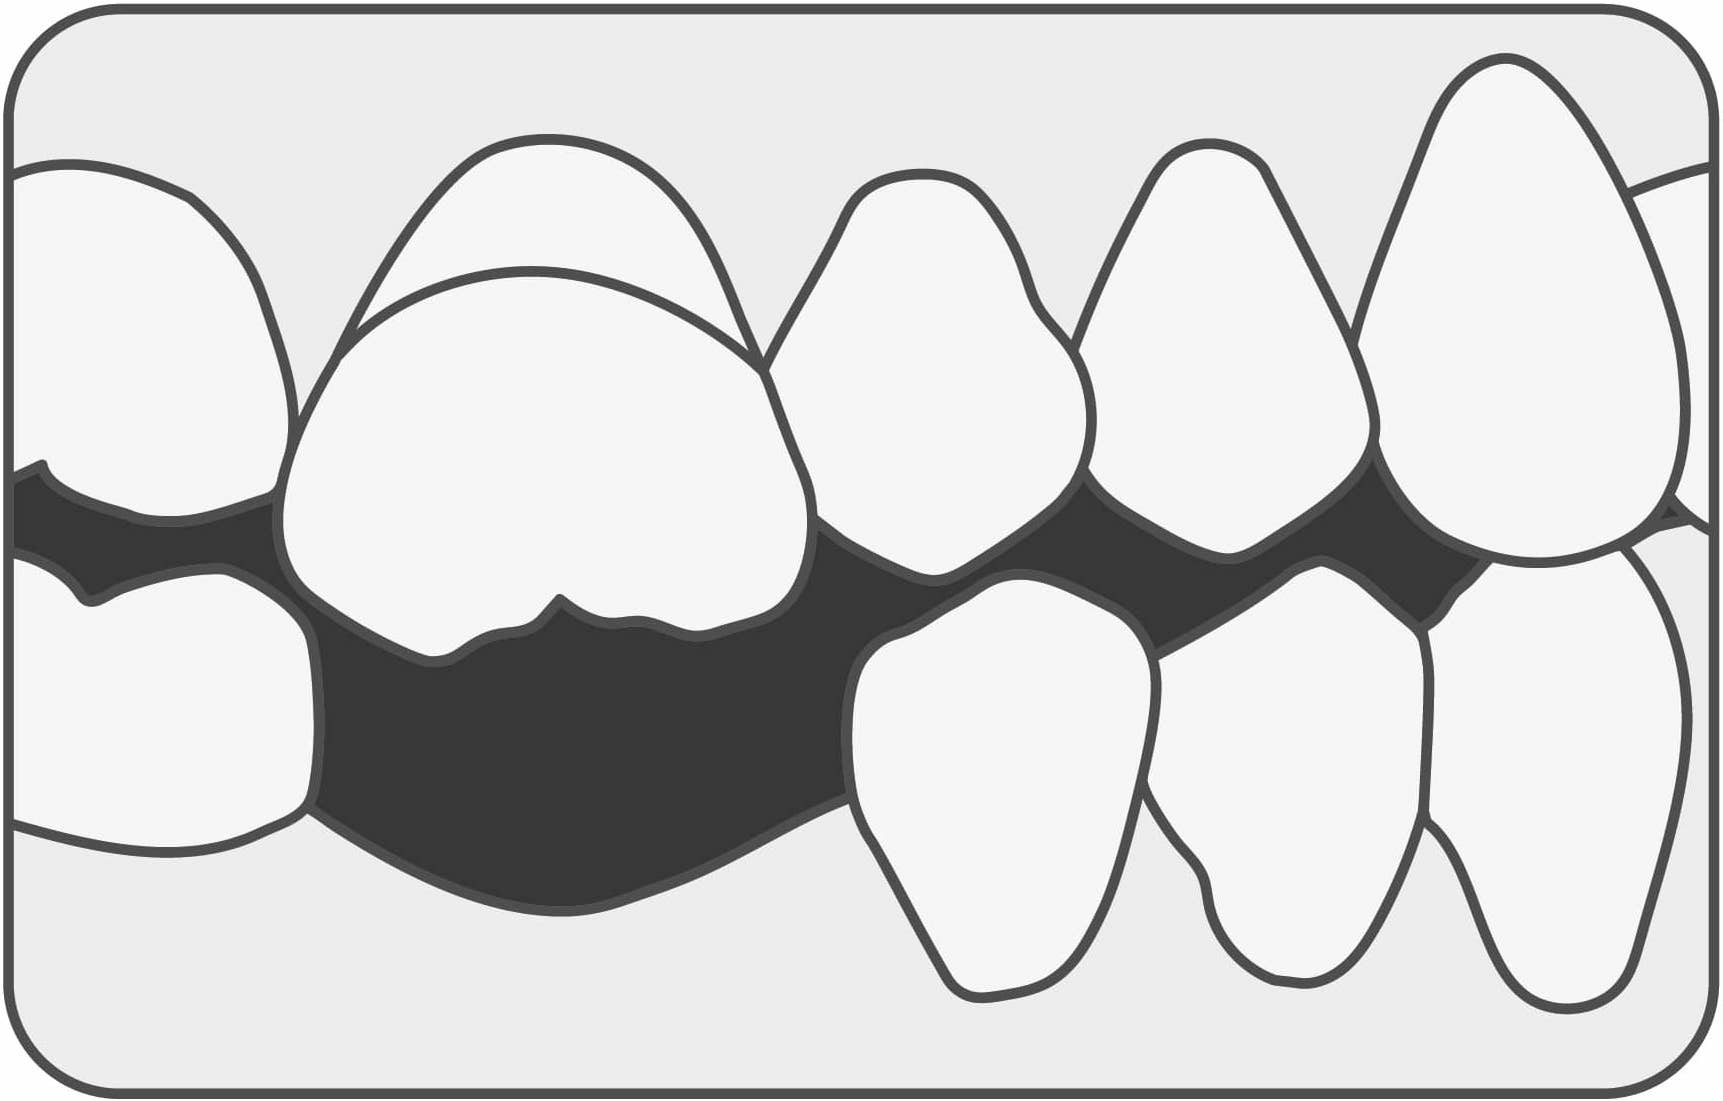

La boca funciona en óptimas condiciones cuando todos los dientes están presentes, alineados y sanos. De esta manera, la fuerza masticatoria se distribuye correctamente.

Cuando una o más piezas dentarias están ausentes, las remanentes deben soportar mayor carga oclusal, quedando expuestas a fisuras, fracturas o daño periodontal.

Los espacios que dejan las piezas perdidas hacen que las demás migren hacia esas zonas, cambiando su dirección, perdiendo soporte óseo, alterando la oclusión y dejando espacios abiertos entre piezas vecinas, lo que genera empaquetamiento de alimentos y por ende mayores posibilidades de tener caries.